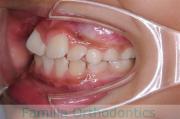

歯並びを治したいということで来院されました。下あごがやや右側に偏位して後退している、上顎前突(出っ歯)でした。上下左右から小臼歯を抜歯して、歯科矯正用アンカースクリューを併用したマルチブラケット法にて治療を行いました。約2年、24回の来院をしていただきました。

下顎の後退はいびきなどの上部気道の障害が出やすいと考えられます。